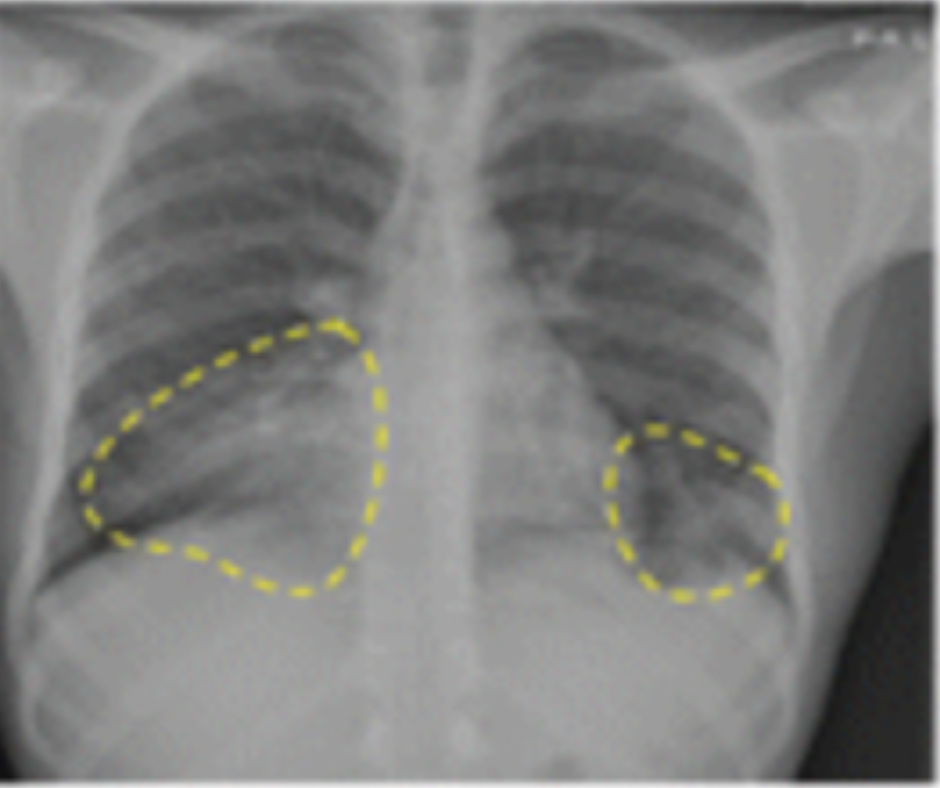

The automated measurement of heart ventricle diameters and detection of potential dilation in the right ventricle may facilitate quicker intervention in cases of pulmonary embolism.